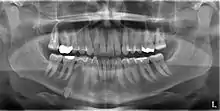

An impacted tooth is one that fails to erupt into the dental arch within the expected developmental window. Because impacted teeth do not erupt, they are retained throughout the individual's lifetime unless extracted or exposed surgically. Teeth may become impacted because of adjacent teeth, dense overlying bone, excessive soft tissue or a genetic abnormality. Most often, the cause of impaction is inadequate arch length and space in which to erupt. That is the total length of the alveolar arch is smaller than the tooth arch (the combined mesiodistal width of each tooth). The wisdom teeth (third molars) are frequently impacted because they are the last teeth to erupt in the oral cavity. Mandibular third molars are more commonly impacted than their maxillary counterparts.

Classifications enable the oral surgeon to determine the difficulty in removal of the impacted tooth. [9] The primary factor determining the difficulty is accessibility, which is determined by adjacent teeth or other structures that impair access or delivery pathway. The majority of classification schemes are based on analysis on a radiograph. The most frequently considered factors are discussed below.